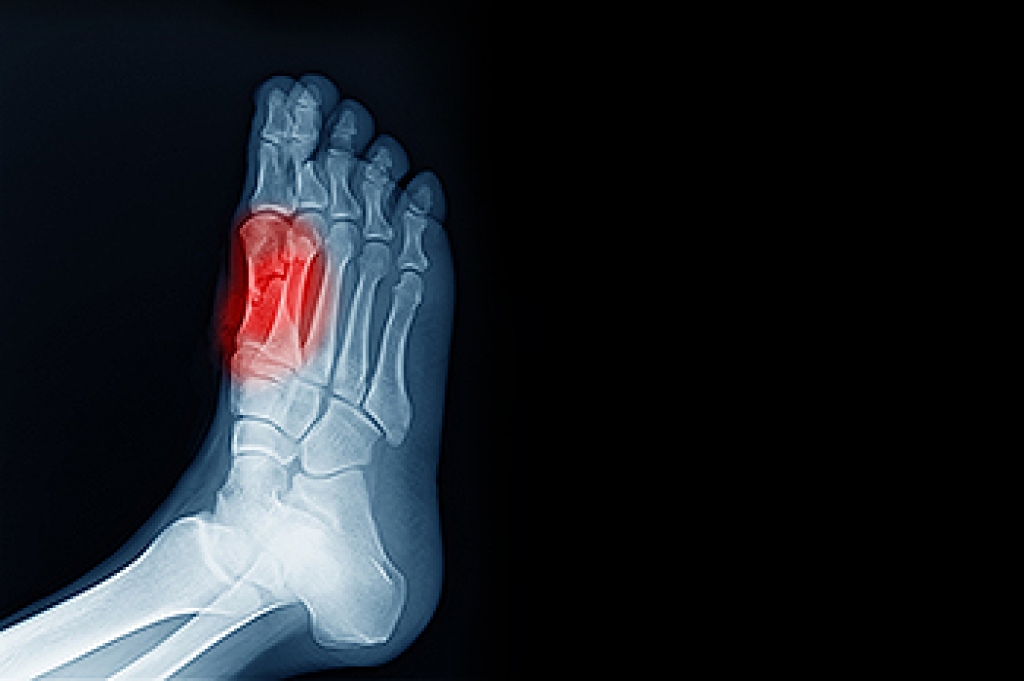

Sesamoiditis is a painful foot condition that affects the sesamoid bones, which are two small bones located beneath the base of the big toe. These bones help absorb pressure and assist with movement during walking and push off. When they become inflamed, pain can develop around the ball of the foot, especially under the base of the big toe. Common symptoms include aching or sharp pain while walking, standing, or bending the toe, along with swelling and tenderness in the area. Sesamoiditis is often caused by repetitive stress, high impact activities, or increased pressure on the forefoot. A podiatrist can diagnose the condition, recommend activity modification, provide protective padding or orthotics, and develop a treatment plan to reduce inflammation. If you have pain under your big toe, it is suggested you schedule a visit with a podiatrist who can accurately diagnose and treat what may be going on.

Sesamoiditis is a condition of the foot that affects the ball of the foot. It is more common in younger people than it is in older people. It can also occur with people who have begun a new exercise program, since their bodies are adjusting to the new physical regimen. Pain may also be caused by the inflammation of tendons surrounding the bones. It is important to seek treatment in its early stages because if you ignore the pain, this condition can lead to more serious problems such as severe irritation and bone fractures.